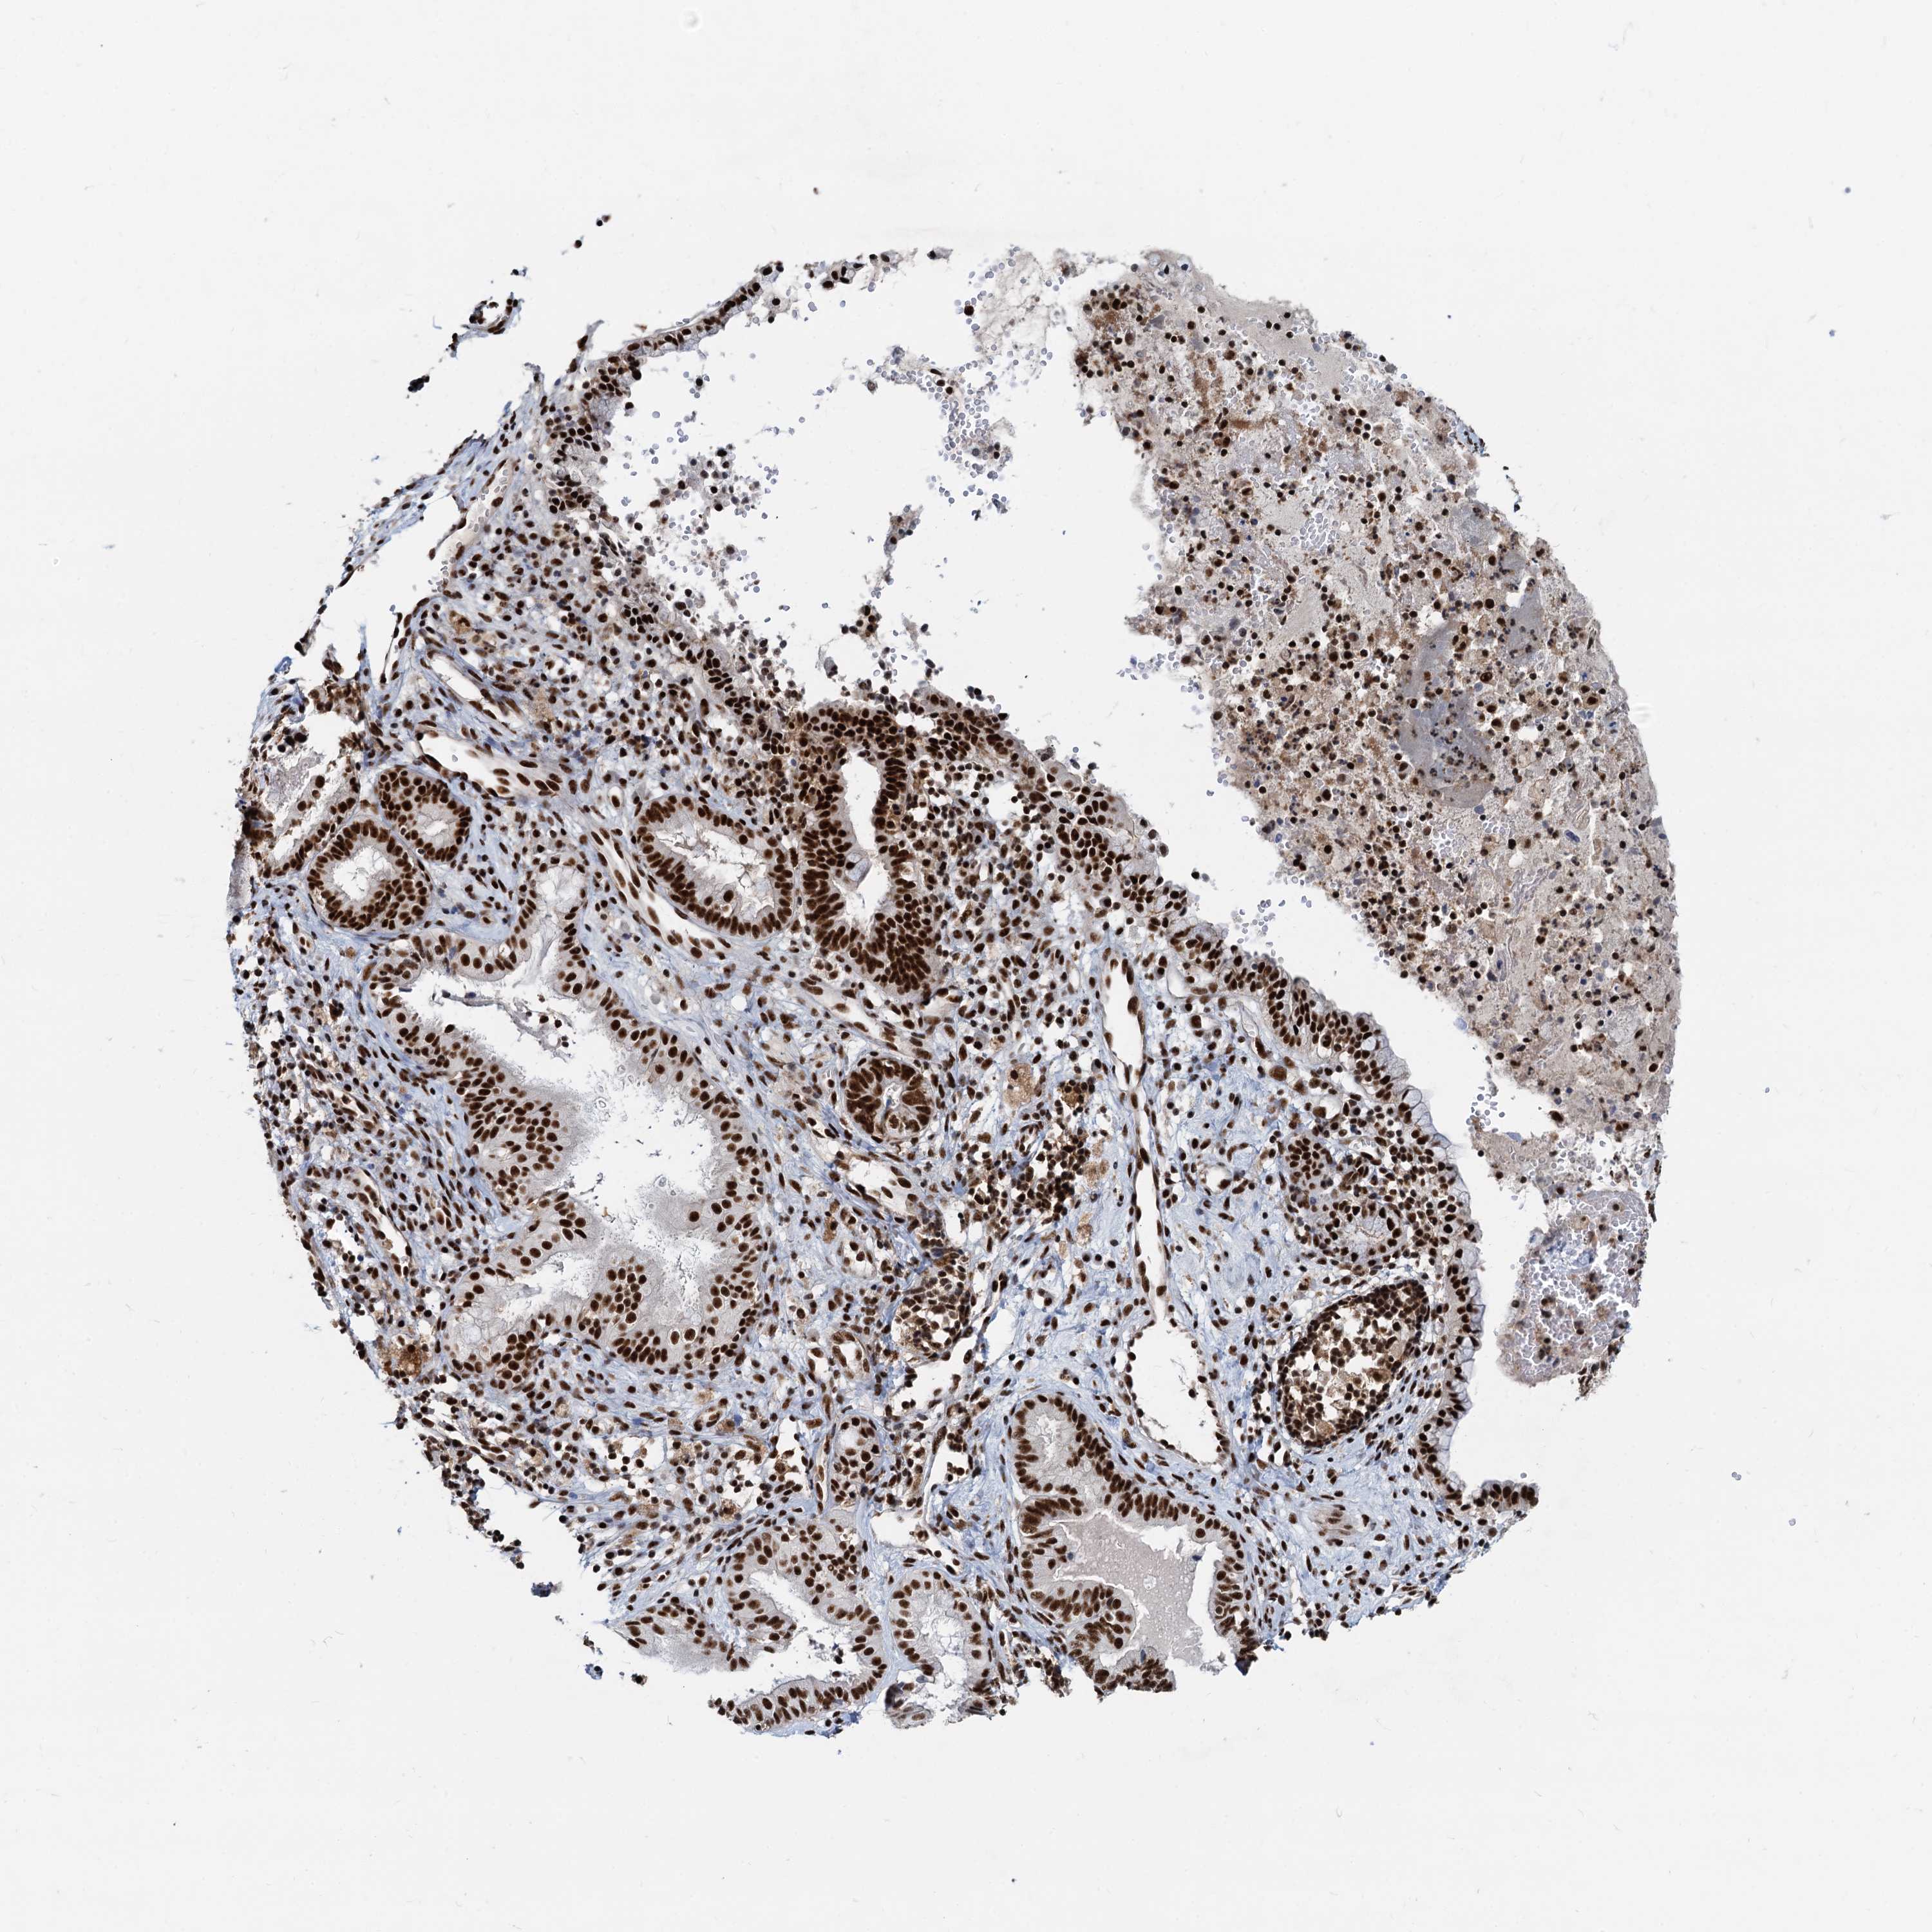

ENDOMETRIAL CANCER - Protein expressioni

A mouse-over function shows sample information and annotation data. Click on an image to view it in a full screen mode. Samples can be filtered based on level of antibody staining by selecting one or several of the following categories: high, medium, low and not detected. The assay and annotation is described here.

Note that samples used for immunohistochemistry by the Human Protein Atlas do not correspond to samples in the TCGA dataset.

Antibody stainingi

Antibody staining in the annotated cell types in the current human tissue is reported as not detected, low, medium, or high, based on conventional immunohistochemistry profiling in selected tissues. This score is based on the combination of the staining intensity and fraction of stained cells.

Each image is clickable and will lead to virtual microscopy that enables deeper exploration of all samples and also displays staining intensity scores, fraction scores and subcellular localization as well as patient and tissue information for each sample.

Antibody HPA040252

Staining

High

Medium

Low

Not detected

Intensity

Strong

Moderate

Weak

Negative

Quantity

>75%

75%-25%

<25%

None

Location

Nuclear

Cytoplasmic/membranous

Cytoplasmic/membranous,nuclear

Adenocarcinoma, NOS

Adenocarcinoma, metastatic, NOS